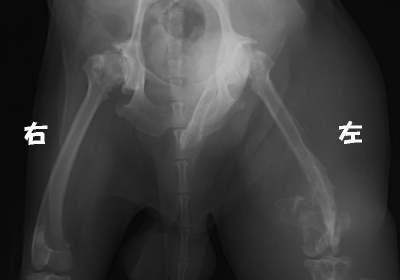

組織球肉腫

非常に悪性度の高い腫瘍の1つです。腫瘍によって左脚の骨が破壊され骨折しています。

周りの組織も右脚の倍くらいに腫れ上がっています。